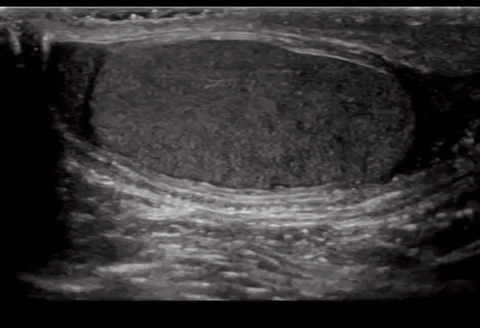

The appendix testis is a vestigial remnant of the Müllerian duct. It is a little nub of non functioning tissue that is normally located in the superior pole of the testicle. If this structure twists (torsion) it can lead to inflammation and pain. This process is most commonly seen in pediatrics especially prepubescent boys.

Clinically there will be pain, in some case epididymitis can develop. The normal appendage is not normally seen in routine scans, though it may reveal itself if there’s a hydrocele. There may also a “blue dot sign” which is a palpable, tender nodule that appears blue/purple under the skin on close inspection.

It is thought that once this tissue becomes necrotic it detaches from the tesis to be a freely moving object in the tunica vaginalis, it then undergoes calcification leading the o scrotal pearl (aka scrotolith).

This is condition is self limiting and does not require surgery. It is typically treated with rest and analgesics/anti-inflammatory medication.